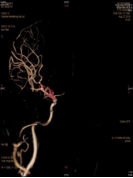

3天前无明显诱因突发剧烈头痛、恶心呕吐,神志清于2018年8月16日由外院转入青岛大学附属医院,CT示鞍上池中等量出血,以右侧侧裂池出血明显多。DSA和CTA示右侧ICA内侧壁有类圆形的囊状膨出,术前考虑为血泡样动脉瘤,术前Hunt-Hess分级II级。